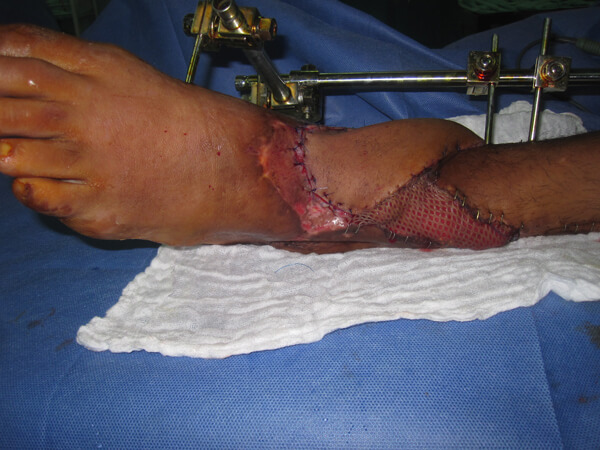

Acute shortening and adjustment of the external fixator was followed by the raising of a fasciocutanteous flap on a single proximal perforator. The flap rotated easily to cover the fracture site. The donor site and any remaining medial and lateral soft tissue wounds were closed using SSG (Figure 11).

Figure 11: Medial, proximally based perforator-plus flap is used to cover exposed bone after thorough

debridement, washout and bone shortening. Skin graft covers the flap donor site and lateral wound.